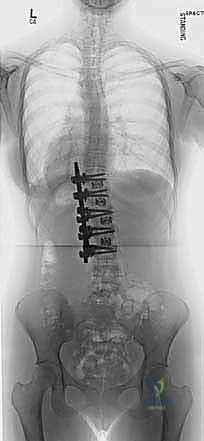

2. التصوير بالأشعة السينية (X-Rays)

هو المعيار الذهبي لتشخيص الجنف. يتم التقاط صور شعاعية لكامل العمود الفقري (من الرقبة إلى الحوض) من الأمام والخلف والجانب، والمريض في وضع الوقوف. من خلال هذه الصور، يقوم الدكتور هطيف بـ:

* قياس زاوية كوب (Cobb Angle): وهي الزاوية التي تحدد شدة الانحناء. الانحناءات الأكبر من 10 درجات تُعتبر جنفاً.

* تقييم النضج العظمي (Risser Sign): من خلال فحص عظام الحوض لمعرفة ما إذا كان المريض لا يزال ينمو، مما يساعد في التنبؤ باحتمالية تدهور الانحناء.

* للتخطيط الجراحي الدقيق (CT Scan) للحصول على نموذج ثلاثي الأبعاد للفقرات المشوهة، مما يساعد في تحديد مسار البراغي بدقة جراحية فائقة.

| التدخل الجراحي (الدمج الفقري) | انحناءات شديدة (أكبر من 45-50 درجة)، أو انحناءات تتدهور بسرعة رغم استخدام الحزام. | تصحيح التشوه، دمج الفقرات لمنع التدهور المستقبلي، واستعادة التوازن. | إجراء الجراحة بأعلى معايير الأمان العالمية باستخدام تقنيات متقدمة. |

2. التخطيط الجراحي المتقدم

لا يدخل الدكتور هطيف غرفة العمليات دون خطة هندسية دقيقة. يتم دراسة صور الأشعة المقطعية والرنين المغناطيسي، وتحديد حجم ونوع البراغي والقضبان المناسبة بدقة المليمتر، ومحاكاة التصحيح المتوقع.